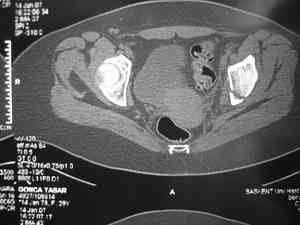

Обследование дополнительными снимками: прямая, инлет и оутлет, а КТ срезы покажет имевшиеся мозольные перемычки и истинное смещение в крестцово подвздошном сочленении.

Дорогой Андрей. Мы имеем дело с комбинированной (ротационно и вертикально) нестабильностью таза со смещением правого гнемипелвиса. При таких переломах, фиксация только переднего полукольца вне зависимости от метода фиксации, как уже было сказано Djoldas Kuldjanov, M.D., не может создать адекватной фиксации. И перелом пластины был вполне ожидаемым после активизации пациента. Смещение сохраняется, и по-видимому не 2 см., а все 4, если не более. Разница всего (+2 см) по конечностям как вы указываете, скорее скомпенсировано позвоночником и протезом. Дополнительные снимки или КТ исследование помогли бы уточнить степень смещения с точностью до мм., выявить перелом поперечного отростка пятого поясничного позвонка, или помимо разрыва правого крестцово-подвздошного сочленения выявить перелом боковой массы крестца справа и т.д. При возможности, конечно, все это желательно сделать. Но мало что изменится с практической точки зрения, т.к. задача - это низведение репозиция и надежная фиксация правого гемипелвиса. Учитывая плачевный опыт стержневого аппарата, давность травмы совершенно очевидно, что поставленная задача достижима при открытой репозиции и одномоментной фиксации переднего полукольца с артродезированием правого крестцово-подвздошного сустава. Операция выполняется в положении больного на здоровом боку или полубоку из расширенного трансоссального подвздошно-пахового доступа с переходом на лонное сочленение доступом по Pfannenstiel. Указанный доступ обеспечивает подход к крестцово-подвздошному сочленению как спереди так и сзади. После артродезирования выполняется синтез лонного сочленения. Клинический пример

закрыто или открыто, а позволит ли Вам это сделать оссифицированная связка? Без подробного КТ лечение застарелой травмы таза обречение пациента и врача на множество неприятных и "неожиданных" открытий.

Доведите диагностический процесс до конца (КТ, функциональные снимки я уж не говорю про сандартные Outlet и inlet), поищите другой источник болей (поясница например).